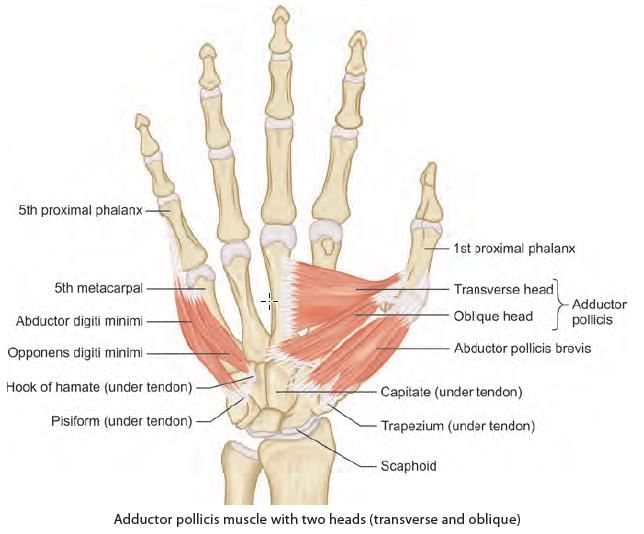

Mention the nerve supply of the marked muscle: (INI-CET May 2022)